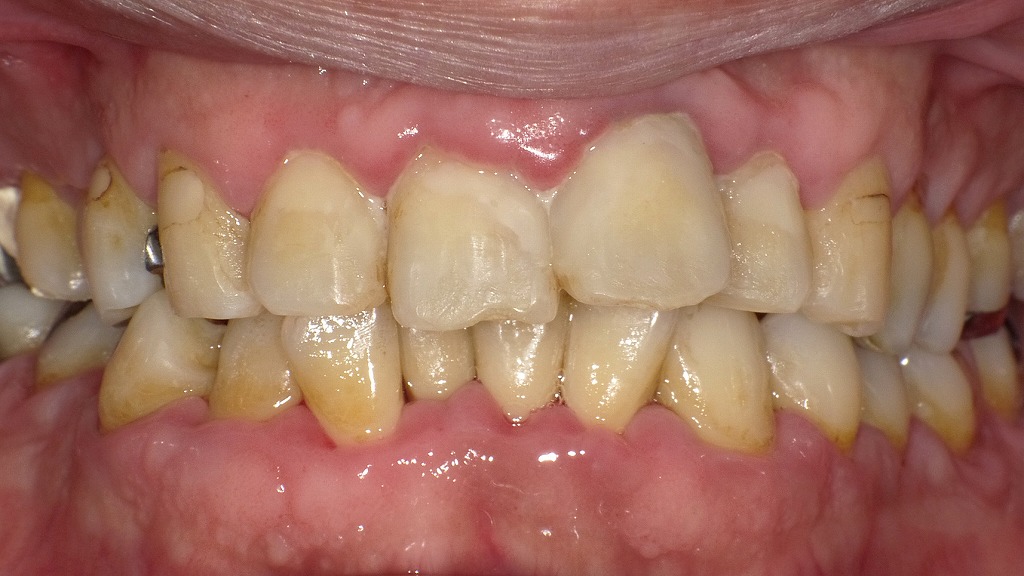

術後:歯周病に罹患している症例

この画像は、同症例の写真(歯石・ヤニ・歯垢が多く付着していた状態)の治療後の状態を示しています。以下のような改善が確認できます。

🔹1. 歯石除去後の状態

歯と歯ぐきの境目にあった茶色い歯石が除去されています。

スケーリング(歯石取り)によって、歯面が清潔になり、歯肉炎症が大幅に軽減しています。

🔹2. ブラッシング指導による効果

患者さん自身のセルフケアの質が向上したことで、歯垢の再付着が減少。

歯ぐきの腫れや赤みが改善し、全体的に引き締まった健康的な歯肉が見られます。

🔹3. 一部に出血が残る

奥歯付近など、一部の歯間部にわずかな歯肉出血の跡が確認されます。

これはまだ軽度の炎症が残っているためで、継続的なブラッシングと定期清掃で改善が期待できます。

🔹4. エアフローによるステイン除去

前回の写真で目立っていたヤニ・茶渋によるステインがほぼ除去されています。

歯面の色調が均一になり、自然な白さが回復しています。

🔹5. 歯肉の改善と退縮(歯ぐきが下がる)

炎症が治まるとともに、歯肉が引き締まり下がって見える部分があります。

これは「歯ぐきが健康を取り戻した証拠」でもありますが、

見た目上、**歯が長く見える(歯肉退縮)**ことがあります。

進行を防ぐために、正しいブラッシング圧と定期メンテナンスが大切です。

🔹まとめ

- 歯石除去とエアフローで清潔な口腔環境に改善

- 炎症が減り、歯ぐきの色が健康的なピンク色に回復

- 一部に出血が残るが、今後のケアでさらに改善可能

- 歯肉退縮は炎症改善後の自然な変化であり、経過観察が必要

📸このように、定期的な歯科クリーニングと正しいブラッシングで、

中等度歯周病でも大きく改善が見られます。